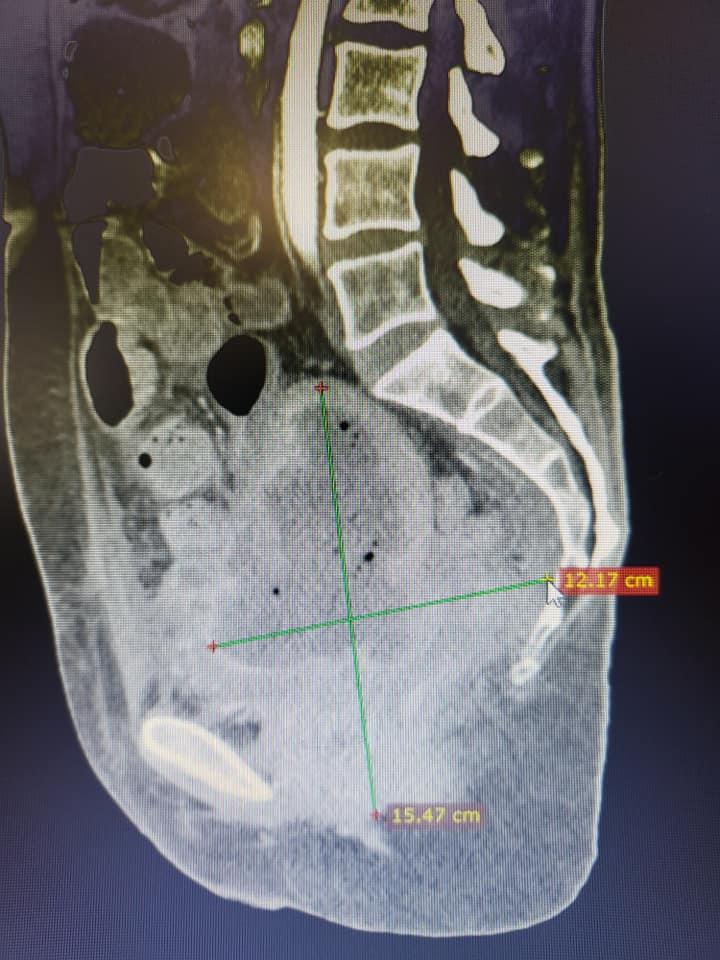

Tânără de 37 de ani trimisă să moară, salvată de medicii din Brașov: De cele mai multe ori imposibilul e posibil! | Galerie Foto | Imagine 2

Facebook Bogdan Moldovan